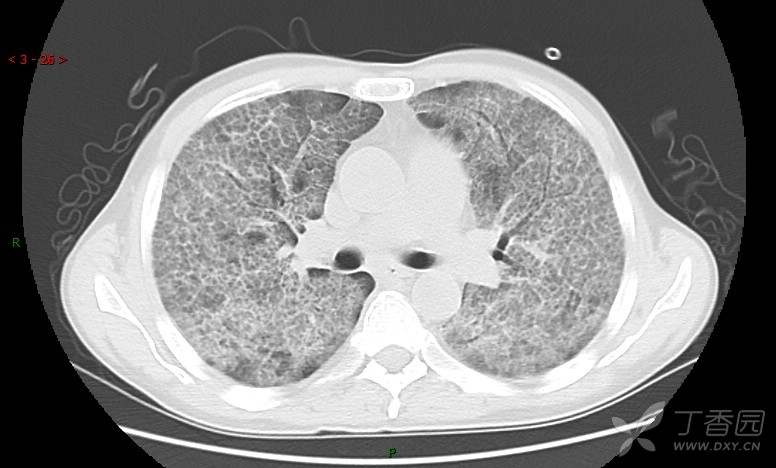

地图+铺路石征=PAP?那升高的CEA怎么说(病例3连发,附其他2例链接)

患者男,42岁,咳嗽半年余,加重伴憋喘2月余。

患者半年余前无明显诱因出现间断咳嗽,干咳为主,偶咳少量黄白痰,剧烈咳嗽或运动后可出现轻度憋喘,无高热、脓臭痰,无胸痛、咯血及晕厥,无低热乏力及盗汗,无心前区压榨感及夜间阵发性呼吸困难,初未在意,未予正规诊治。2月余前患者自觉上述症状较前加重,咳嗽、憋喘明显,黄白色粘痰略有增多,伴有发热,热前伴有畏寒、寒战,体温最高达38.9℃,先后就诊多家医院,入住重症监护室,未行气管插管,考虑“重症肺炎”,给予“美罗培南、复方磺胺甲噁唑”等药物抗感染,“卡泊芬净”抗真菌,并给予“甲泼尼龙”等药物治疗35天,经治疗后症状好转于2018-04-02出院。患者自出院后仅应用中药治疗(具体不详),并给予家庭氧疗,平素仍有间断咳嗽,咳少量黄白色粘痰,活动后憋喘明显,活动耐量差,以卧床为主。

肺内弥漫性网状结节影,PET-CT却无阳性病灶,这是?(附其他2例链接)